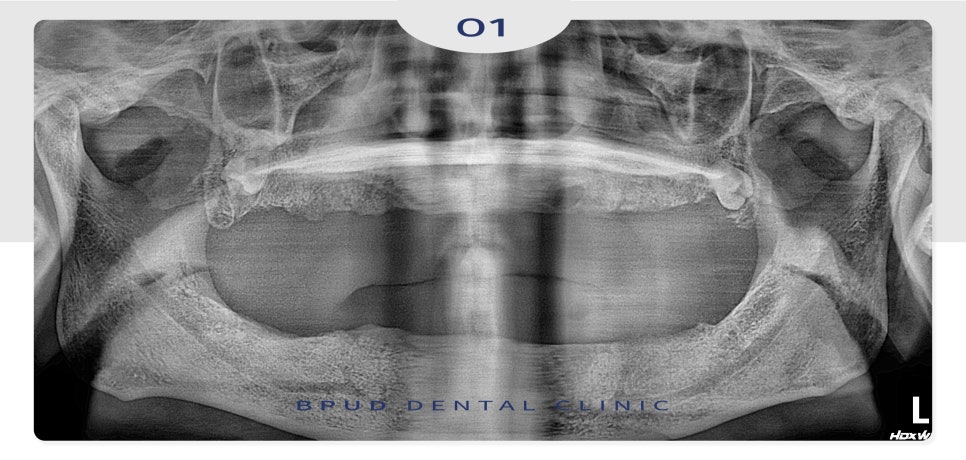

오늘은 오랫동안 전체 틀니를

사용하시다가 부평치과 전체임플란트로

교체하신 환자분을 소개해 드리겠습니다.

위 환자분께서는 오래전부터

틀니를 사용하셨지만 쉽게 빠지고

잇몸이 눌려 통증으로 장착이 어려워

식사를 거의 못하시게 되었다고 말씀하시며

임플란트로 교체를 희망하셔서

직접 인터넷으로 부평치과 전체 임플란트를

검색해 보시고 전화로 상담 후 내원해 주셨습니다.

전체적인 수복을 원하셨기 때문에

3D CT를 통한 면밀한 진단을 통해

위쪽 12개, 아래쪽 9개의 임플란트를

수복하기로 계획을 수립하였는데요.

아래쪽은 신경의 위치를 고려하여

작은 어금니 부위는 인공치아로 대체하였고

오랜 기간 틀니의 사용으로

전체적으로 많이 흡수가 진행된

잇몸뼈는 치조골 이식을 통해

회복하기로 하였습니다.